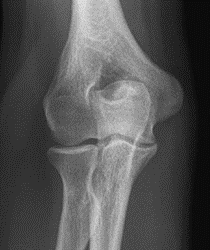

Świadczenie usług medycznych …

Radiogram przedstawia

Ilustracja do pytania 19

A. ciężki uraz miednicy w mechanizmie stycznym.

B. prawidłową miednicę 10-letniego chłopca w ocenie panewki.

C. prawidłową miednicę u osoby starszej w ocenie panewki.

D. złamanie w obrębie szyjki kości udowej z przemieszczeniem linii Shentona.